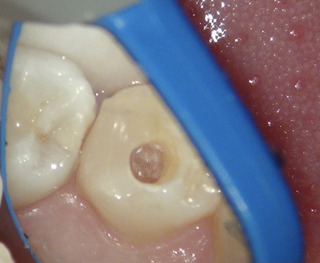

もしや‥もう一つ根管があるのかも?!

と思い、狭い歯の中を拡大していくと‥

やはりありました。もう一つの根管。

1根じゃなく2根管だったのね。

これで透過像の謎が解けました。

赤丸が2根管目。